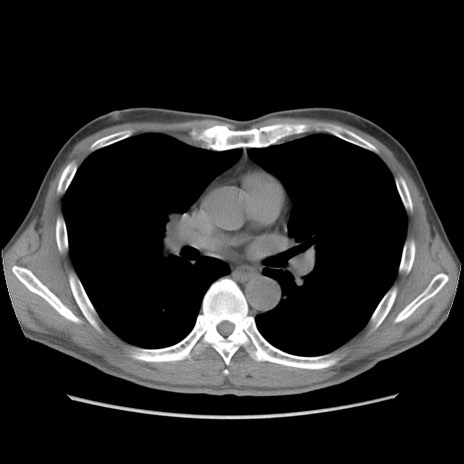

症例56 CT(横断像)

脂肪ウインドウ